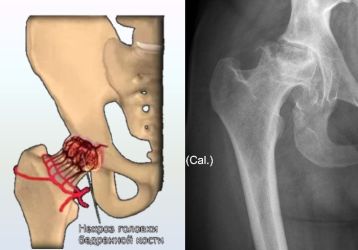

Асептический некроз головки бедренной кости: причины, симптомы, лечение

Асептический некроз головки бедренной кости: причины появления болезни, характерные симптомы, диагностика. Лечение некроза тазобедренного сустава.